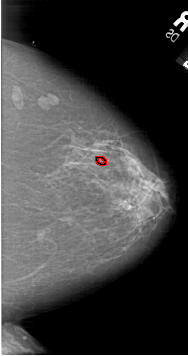

A_1646_1.RIGHT_MLO

RIGHT_CC LINES 6391 PIXELS_PER_LINE 3376 BITS_PER_PIXEL 12 RESOLUTION 43.5 OVERLAY

FILE: A_1646_1.RIGHT_CC.OVERLAY

TOTAL_ABNORMALITIES 1

ABNORMALITY 1

LESION_TYPE CALCIFICATION TYPE PLEOMORPHIC DISTRIBUTION CLUSTERED

ASSESSMENT 3

SUBTLETY 2

PATHOLOGY BENIGN

TOTAL_OUTLINES 1

BOUNDARY